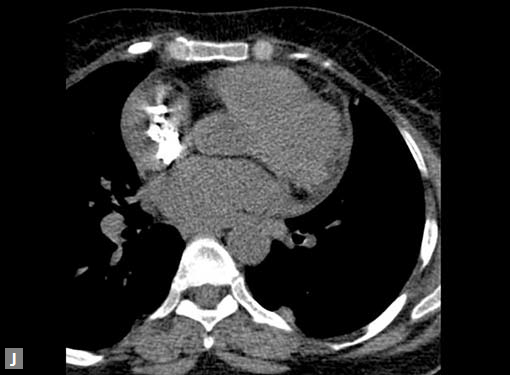

Connective tissue disease, hypertension and iatrogenic (Figs 19K to L) injury are the common causes for dissection. Radiologist not only establishes the diagnosis, also evaluates the extent of dissection, presence of thrombosis particularly in false lumen. In case of type A dissection, involvement of aortic root is determined. Relation of thrombosed lumen and ostia of coronary vessels, cephalad branches (Figs 19N, R to V) of aorta is determined. Most of the occasions membrane is demonstrated. Spiral nature of the membrane can be seen

Pericardial effusion may accompany type A dissection.

Hemopericardium is the dreaded complication of leaking

type A dissection (Figs 19S to V). The type B dissection can

Figs 19A to Y (A to C) Scannogram (A), plain (B) and contrast study (C) show partial anomalous pulmonary venous connection; (D to F) Heterotaxy; (G) Aortic occlusion; (H and I) Aortic stents; (J) Aortic dissection with ‘Benz’ sign due to second dissection within the true lumen; (K, L and M) Aortic dissection with thrombus in pseudolumen following catheter angiogram; (N) Aortic dissection involving common carotid arteries and subclavian artery; (O, P, Q and R) Aortic dissection with right renal artery arising from true lumen and left renal artery from false lumen; (S, T, U and V) Stanford B dissection with extension Y to iliac vessels; (W to Y) Aneurysmal dilation of ascending aorta